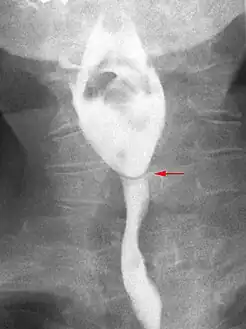

Esophageal web stenosis in barium swallow examination frontal view.

Esophageal webs are thin 2–3 mm (0.08–0.12 in) membranes of normal esophageal tissue consisting of mucosa and submucosa that can partially protrude/obstruct the esophagus. They can be congenital or acquired. Congenital webs commonly appear in the middle and inferior third of the esophagus, and they are more likely to be circumferential with a central or eccentric orifice. Acquired webs are much more common than congenital webs and typically appear in the cervical area (postcricoid).

The diagnostic test of choice is a barium swallow.